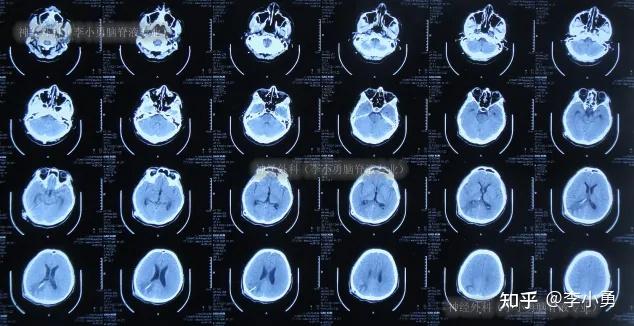

醫(yī)院致力于打造一支由知名專家和中青年學(xué)科帶頭人組成的高素質(zhì)醫(yī)療團隊北京中醫(yī)院掛號指引CT加急,他們傳承并創(chuàng)新中醫(yī)精華,采用中西醫(yī)結(jié)合的治療手段,如中藥針灸推拿等,成功治療各種疑難雜病,在國內(nèi)外享有很高的聲譽在醫(yī)療設(shè)備方面,東直門中醫(yī)院引進(jìn)了國際先進(jìn)的診療設(shè)備,如MRI四排螺旋CTSPECT等,配備了關(guān)節(jié)手術(shù)導(dǎo)航;重點科室骨傷科和糖尿病專科為國家級重點專科,肛腸科針灸科中醫(yī)腫瘤科脾胃科和中醫(yī)婦科為特色科室設(shè)施設(shè)備自2008年與北京中醫(yī)藥大學(xué)合并后,醫(yī)院設(shè)施得到升級,引入了如美國GE螺旋CT飛利浦DR等先進(jìn)醫(yī)療設(shè)備中醫(yī)特色服務(wù)醫(yī)院注重發(fā)揮中醫(yī)藥特色,設(shè)立中醫(yī)特色傳統(tǒng)診療區(qū),提供針灸拔罐;臨床成就 中風(fēng)治療作為北京中醫(yī)醫(yī)院針灸科主任北京市針灸學(xué)科帶頭人,他在學(xué)科建設(shè)中大膽探索,率先成立中醫(yī)卒中單元,采用針灸和中西醫(yī)結(jié)合方法救治中風(fēng)病人,將康復(fù)治療和健康教育融為一體,療效顯著,獲國際公認(rèn)和患者好評曾接診一位瀕臨中風(fēng)患者,CT顯示有中風(fēng)前期癥狀,口齒不清眼歪嘴斜左半身麻木,他采用;診區(qū)采用電子叫號系統(tǒng),按掛號順序就診,人工插隊無效,請耐心等待繳費與報告查詢醫(yī)院支持自助機繳費打印檢查報告,或通過線上查詢檢驗結(jié)果北京醫(yī)保患者需在繳費前完成醫(yī)保分解,否則費用需自付咨詢與幫助各樓層設(shè)有導(dǎo)醫(yī)臺,可協(xié)助患者取號報到及提供流程指引,如有需要可尋求幫助三注意事項;1 北京中醫(yī)醫(yī)院啊這個是公立的三甲中醫(yī)院2 始建于1956年,是北京市唯一的一所市屬綜合性現(xiàn)代化三級甲等中醫(yī)醫(yī)院,承擔(dān)著北京市中醫(yī)醫(yī)療教學(xué)科研預(yù)防等任務(wù)醫(yī)院設(shè)有精神科檢驗科物理診斷科放射科病理科核醫(yī)學(xué)科等醫(yī)技科室,擁有核磁CTECT螺旋CTDSA血管機大型;呼吸科疾病建議選擇當(dāng)?shù)卣?guī)的中醫(yī)醫(yī)院的呼吸內(nèi)科進(jìn)行就診建議最好去醫(yī)院拍個肺部CT檢查,明確診斷平時多喝溫開水,多吃新鮮的蔬菜和水果,飲食宜清淡,不宜吃煎炸及辛辣刺激的食物,不能抽煙喝酒,注意休息,不能勞累,放松壓力,保持愉快心情,室內(nèi)保持空氣流通,避免受涼北京。

北京中醫(yī)藥大學(xué)東直門醫(yī)院以其完善的設(shè)施滿足患者需求,醫(yī)院內(nèi)部設(shè)施配備完善,擁有27個一級臨床科室和5個醫(yī)技科室,提供了豐富的專科專病門診服務(wù),共計92個,每日接待門診量可達(dá)2500多人次醫(yī)院的住院部設(shè)有15個病區(qū),包括EICUSICU和CCU病房,總共提供574張病床,為患者提供了寬敞舒適的住院環(huán)境此外;多位專家提醒,目前大多數(shù)新冠感染者表現(xiàn)為上呼吸道癥狀,并未累及肺部,無需盲目進(jìn)行CT檢查12月24日,北京中醫(yī)醫(yī)院重癥醫(yī)學(xué)科宋麥芬主任正在查看新冠患者肺部CT片曹子豪攝醫(yī)院CT預(yù)約爆滿,患者進(jìn)行CT檢查“為求心安”“近一周來,CT室都沒有人少的時候,這兩天尤其多,掛號等候的患者基本都在四五;首都醫(yī)科大學(xué)附屬北京中醫(yī)醫(yī)院是北京市內(nèi)最杰出的中醫(yī)醫(yī)療機構(gòu)之一建立于1956年,該醫(yī)院座落于東城區(qū)美術(shù)館后街2361號,具備三級甲等醫(yī)院的資質(zhì),承擔(dān)著醫(yī)療教學(xué)科研預(yù)防與保健等多重職能醫(yī)院設(shè)有1400張床位,配備了先進(jìn)的醫(yī)療設(shè)備,如30T磁共振儀256層極速CT數(shù)字平板血管造影系統(tǒng)SPECTCT。